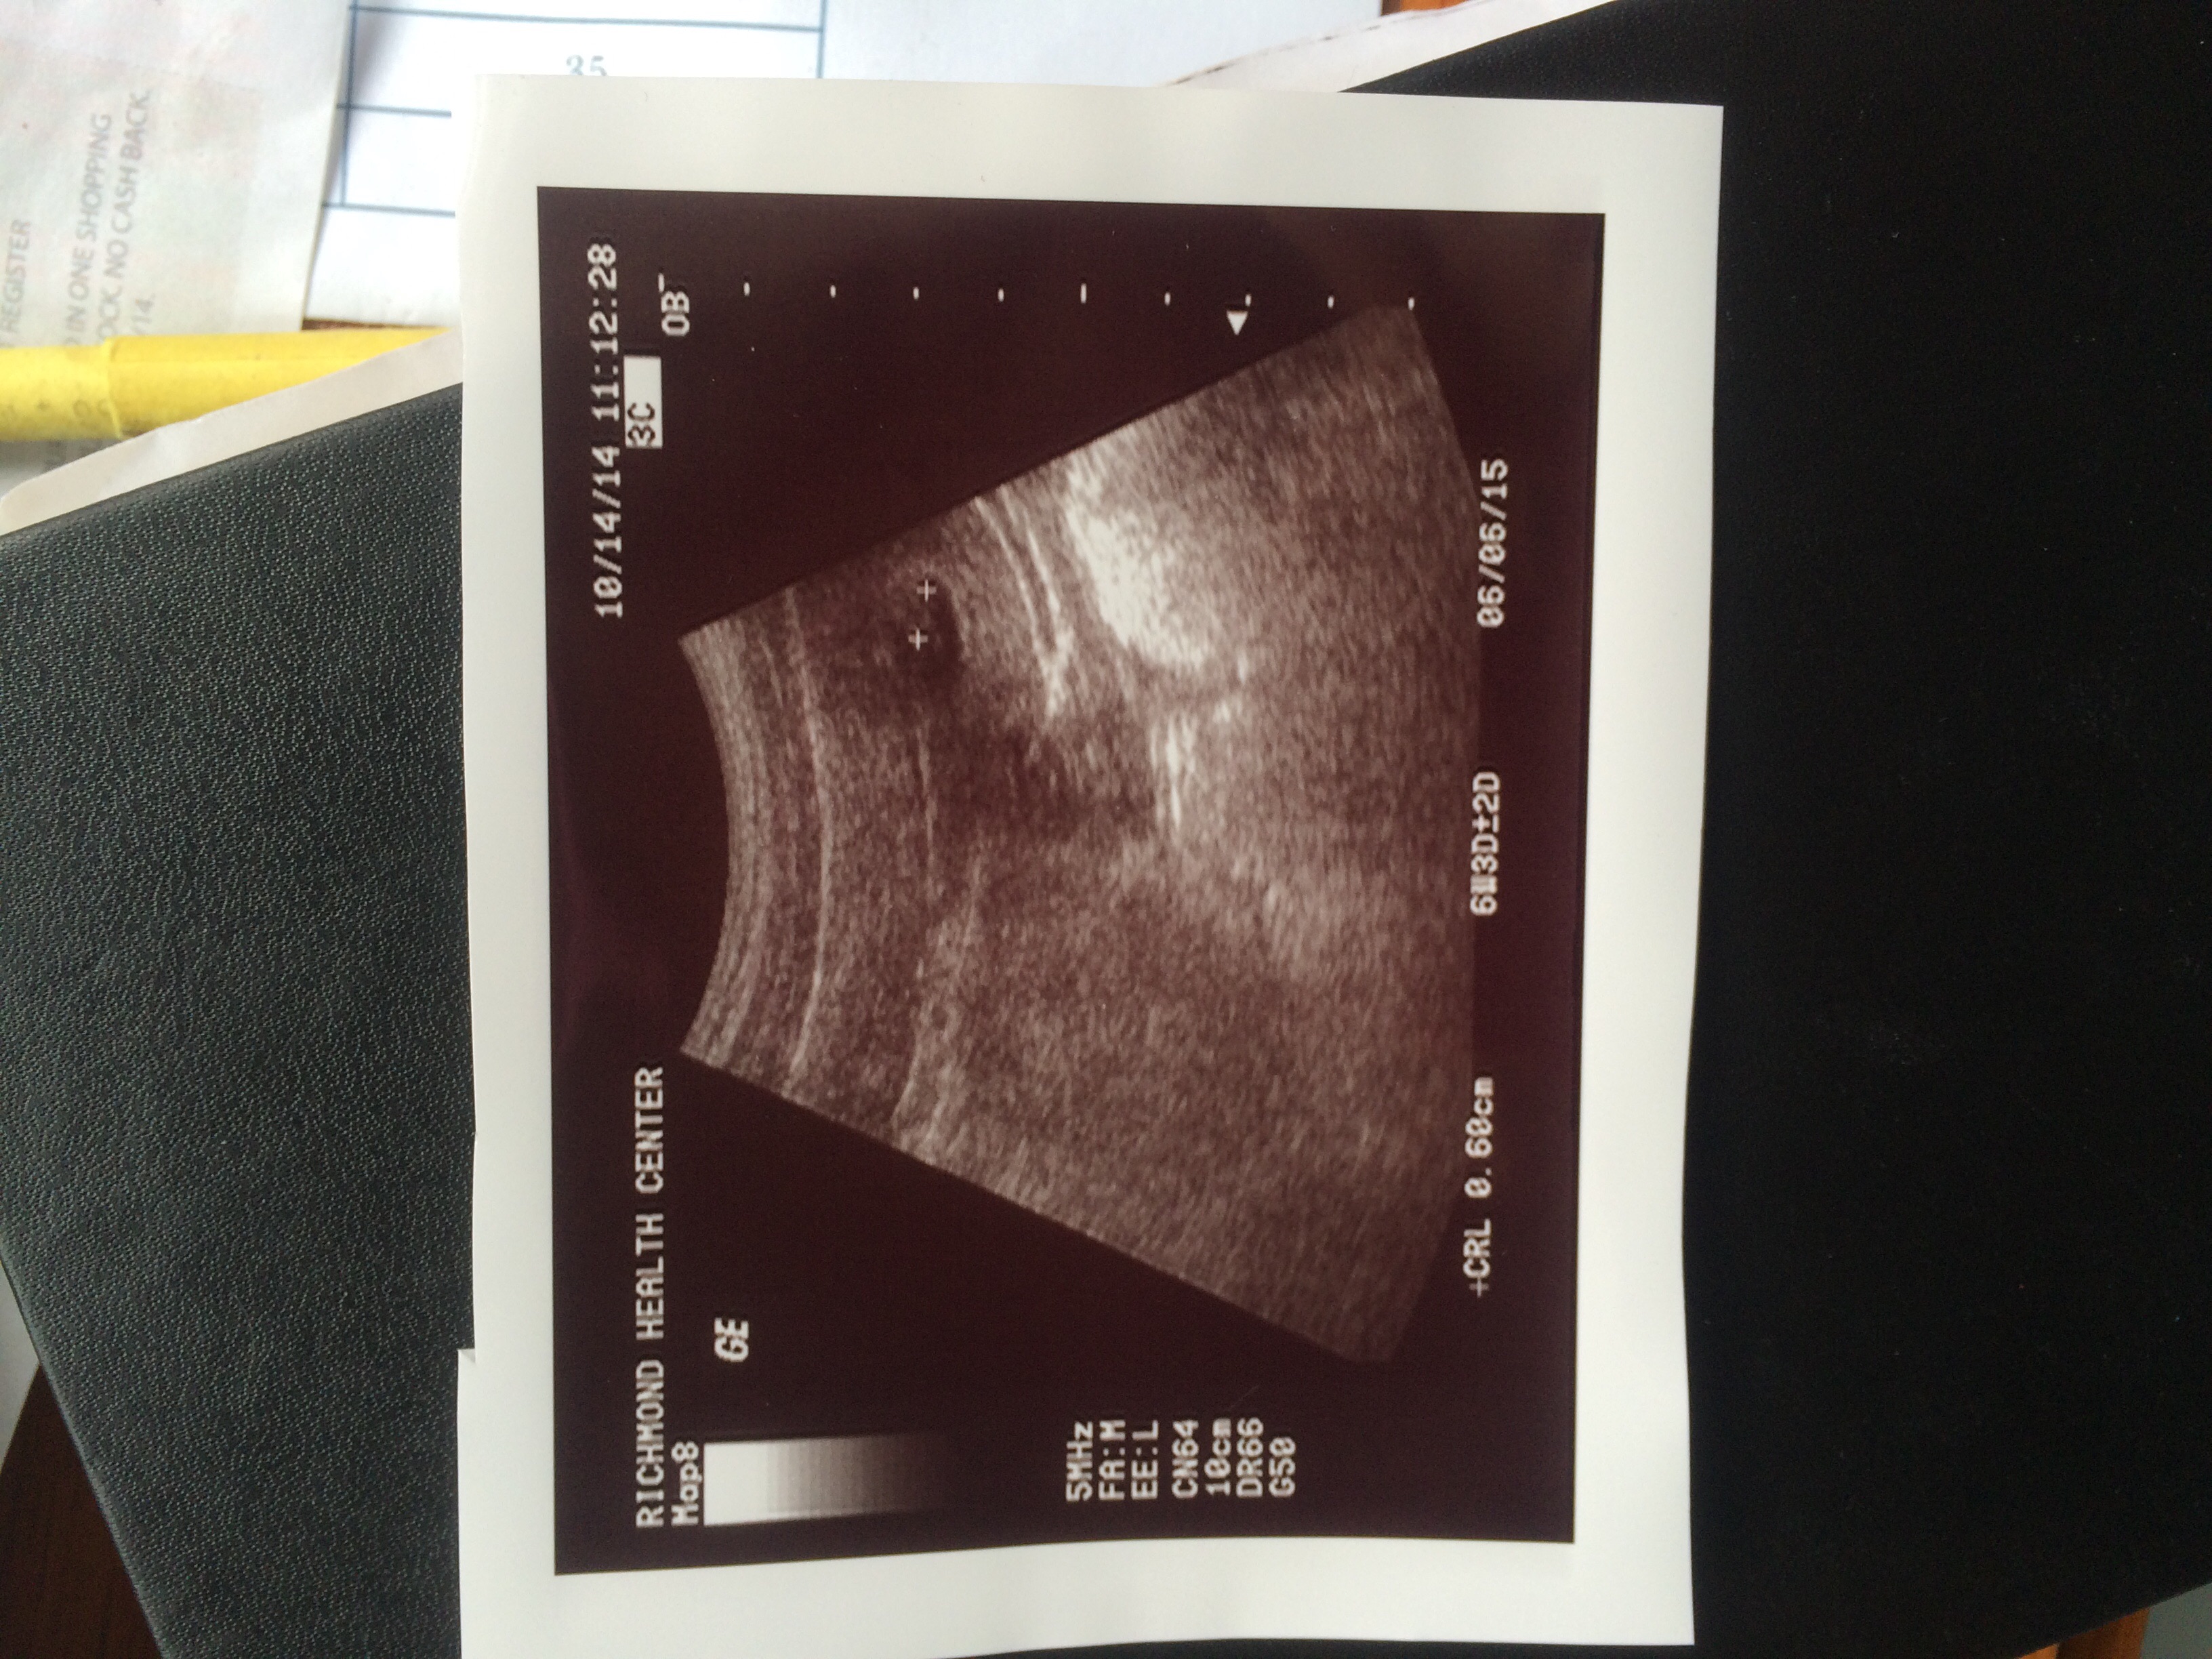

• Here's mine I thought I was 7 weeks but I was 6 weeks 5 days